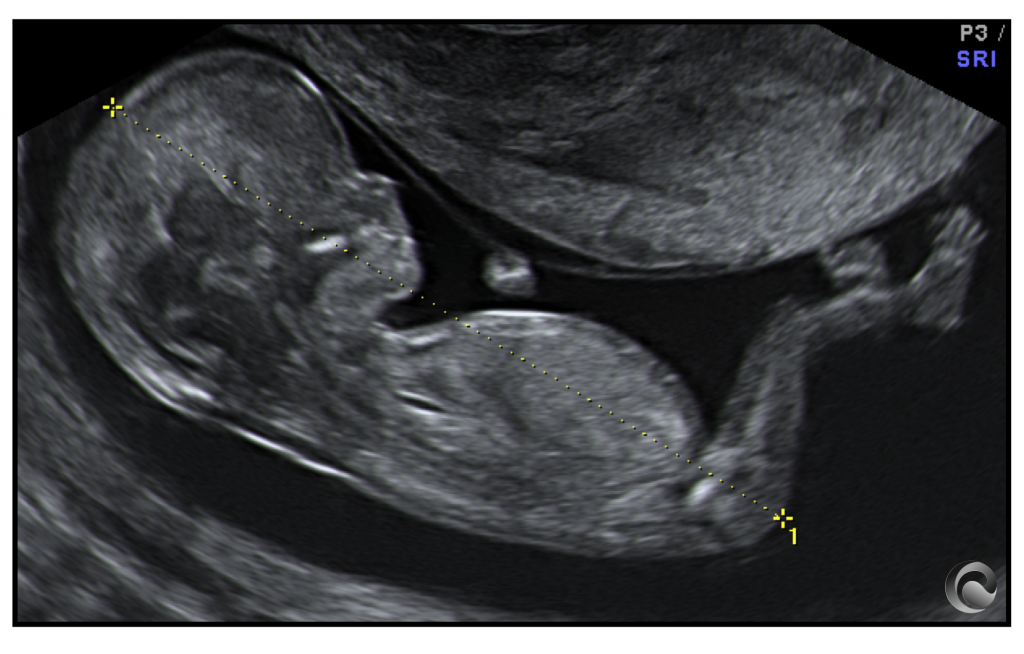

Visión completa tridimensional dinámica («4D») de un feto durante las 11-13 semanas